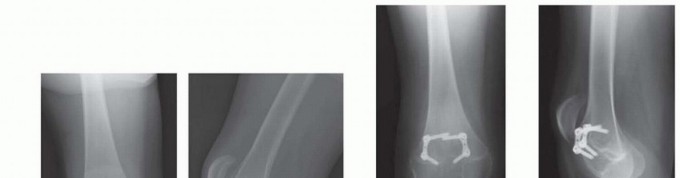

- ###

- FIG 2 • A. A 13-year-old girl with knee pain and difficulty with ambulation secondary to genu valgum. B. Standing AP radiograph of her lower extremities demonstrating bilateral genu valgum with abnormal LDFA bilaterally and an abnormal MPTA on the right tibia. She was indicated for bilateral medial distal femoral

- guided growth and right medial proximal tibia guided growth. C. Standing AP radiograph at 7 month postoperatively demonstrates normalization of her mechanical axis. (Courtesy of UW Pediatric Orthopaedics.)

- Consider placing an implant in an adjacent bone that is normal to accelerate correction of limb deformity. For example, in adolescent Blount disease, it may be necessary to guide growth of both the lateral tibia and lateral femur in an obese patient with less than 2 years of growth remaining.